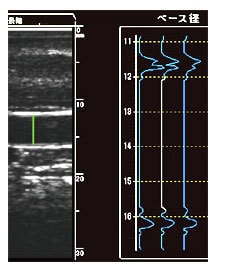

血管径計測は、Bモード画像の5倍の分解能を持つAモード波形による計測を採用することにより 検者間誤差を少なくし、高い再現性を実現しています。

特徴4:トレンドグラフで真の最大拡張径を捉える

駆血開放後、血管が最も拡張する時間は30~90秒程度と個人差があります。 この個人差を、一拍ごとの血管径変化をトレンドグラフで表示する事により、最も血管が拡張した拍を捉えることができます。 これにより、真の最大拡張径によるFMD値の算出を可能としています。